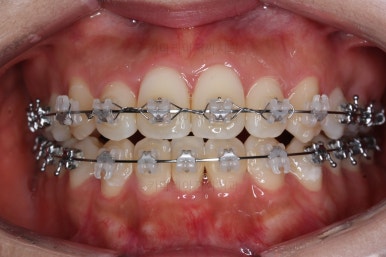

초진 시 입안의 모습입니다.

그냥 봐도 뭔가 애매함이 있죠?

중앙선이 맞지 않고, 교합이 떠보이는 양상이네요.

윗니는 좌측 작은 어금니가 한 개 모자랐고 아랫니는 앞니 하나가 모자라네요.

그런데 앞니는 아랫니가 1개 모자란 채로 교합이 맞춰져서 윗니가 하나 부족한 채로 애매한 상태였어요.